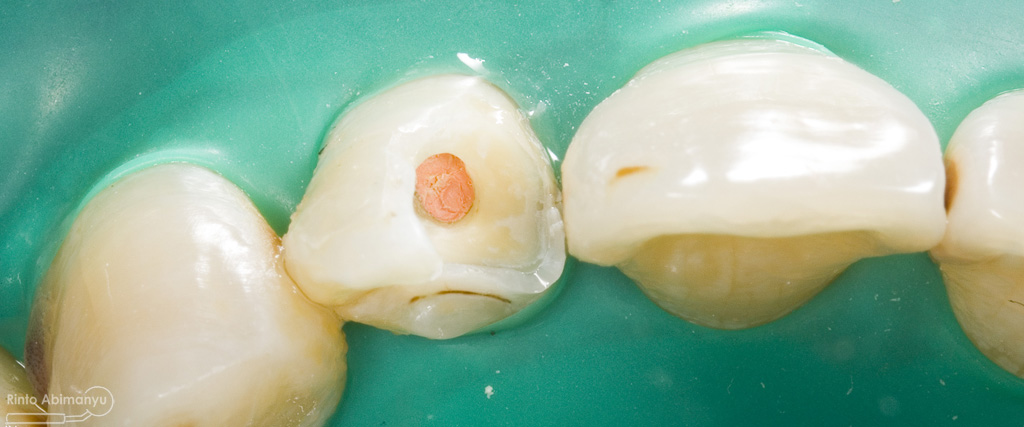

Pertama saya lakukan anestesi infiltrasi dan kemudian memasang rubber dam untuk isolasi daerah kerja, dilanjutkan pembersihan karies dan pembukaan kamar pulpa.. Pada kasus ini pengerjaan dilakukan langsung pada dua gigi…

Setalah pengisian usahakan kamar pulpa dibersihkan dari sisa2 siler dan kotoran2 agar bahan adhesive yang kita pakai untuk restorasi dapat melekat maksimal.. Untuk basis saya menggunakan X-tra Base (Voco) kemudian diatasnya memakai komposit Z 350 XT (3M)…